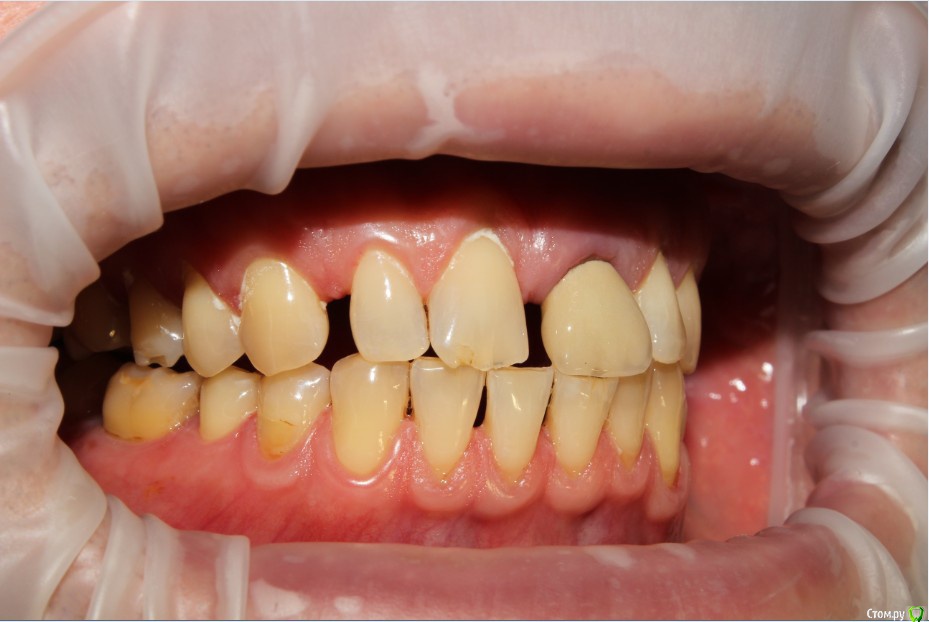

Рустам Опубликовано 20 июля, 2015 Поделиться Опубликовано 20 июля, 2015 Здравствуйте коллеги! Подскажите по клиническому случаю пожалуйста. Обратился пациент в клинику с подвижной коронкой на зубе 2.1, на рентгене диагностирован перелом корня, планируем удаление с одномоментной имплантацией и желательно с немедленной нагрузкой. Система имплантатов "Osstem", на этой системе я ранее не протезировал (работал с "Mis" и "Super Line") и вообще ранее немедленно не нагружал имплантаты. Хирург назначил удаление и иплантацию на 23.07, я смогу принять пациента только 24.07 утром, необходимо заказать временный абатмент, подскажите какой именно из каталога нужно заказать?Имплантолог заказал два имплантата Osstem TSIII SA диаметром 4,0 и 4,5.Я планирую делать временную прямым способом по ключу снятому со старой коронки во рту. Может лучше через оттиск заказать лабораторную временную?P.S. пациента эстетически все устраивало, ортодонтию не хочет. Ссылка на комментарий